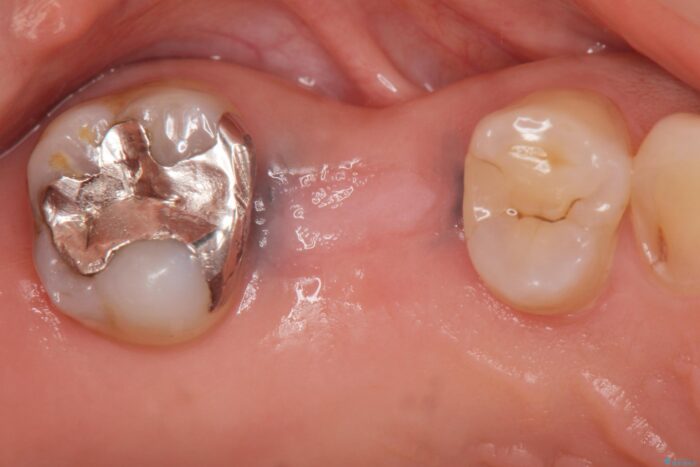

虫歯の悪化により奥歯を失った患者様です。 咬合機能の回復を求めてご相談にいらっしゃいました。

ブリッジ、インプラント、入れ歯による長短所のご説明を行い、インプラント治療を進めていくこととなりました。